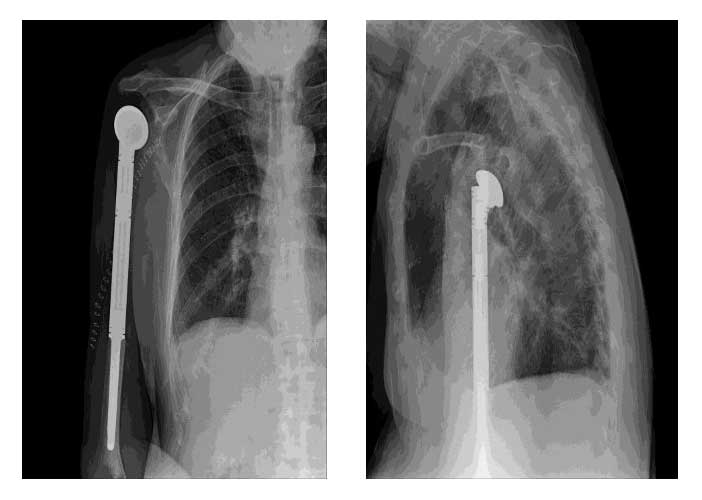

Ameliyat Sonrası: Röntgende çimentolu humerus üst uç tümör protezi görülmekte.